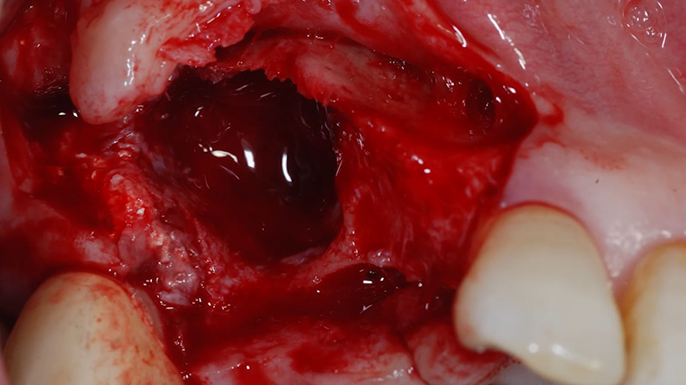

“Prefabricated provisional restorations can serve as custom healing abutments in case of insufficient initial stability for one-day implants. ”

Clinical case: Immediate implant placement using R2GATE Guide & custom healing abutment

- Courtesy of Dr. Sam Omar, Egypt -

Dr. Sam Omar, Digital Guided Surgery, Digital ONE-DAY Implant, Maxillary Posterior, #16, Guided surgery, Loading, Flapless, AnyRidge, R2GATE, MEGA ISQ, R2GATE Full surgical kit

Implant system-AnyRidge, R2 Guide, R2GATE Full Surgical Kit, Mega ISQ,